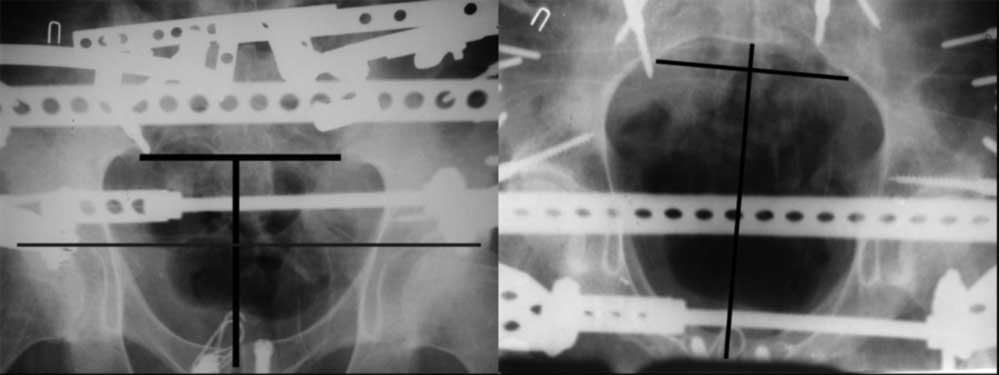

закрытое низведение правой половины таза кольцевым аппаратом (с фиксацией задних отделов), затем проведение илиосакральных винтов, реостеосинтез лонного сочленнения, дальнейшая фиксация в аппрате 2-3 мес. Похожий пример в приложении.

прилагаю пример с такой же давностью травмы, репонировали аппаратом

> в аппарате или одномоментно открыто. Лично я склоняюсь к аппаратному лечению на первом этапе.

задача непростая, если мало опыта в этом деле, подумайте еще раз